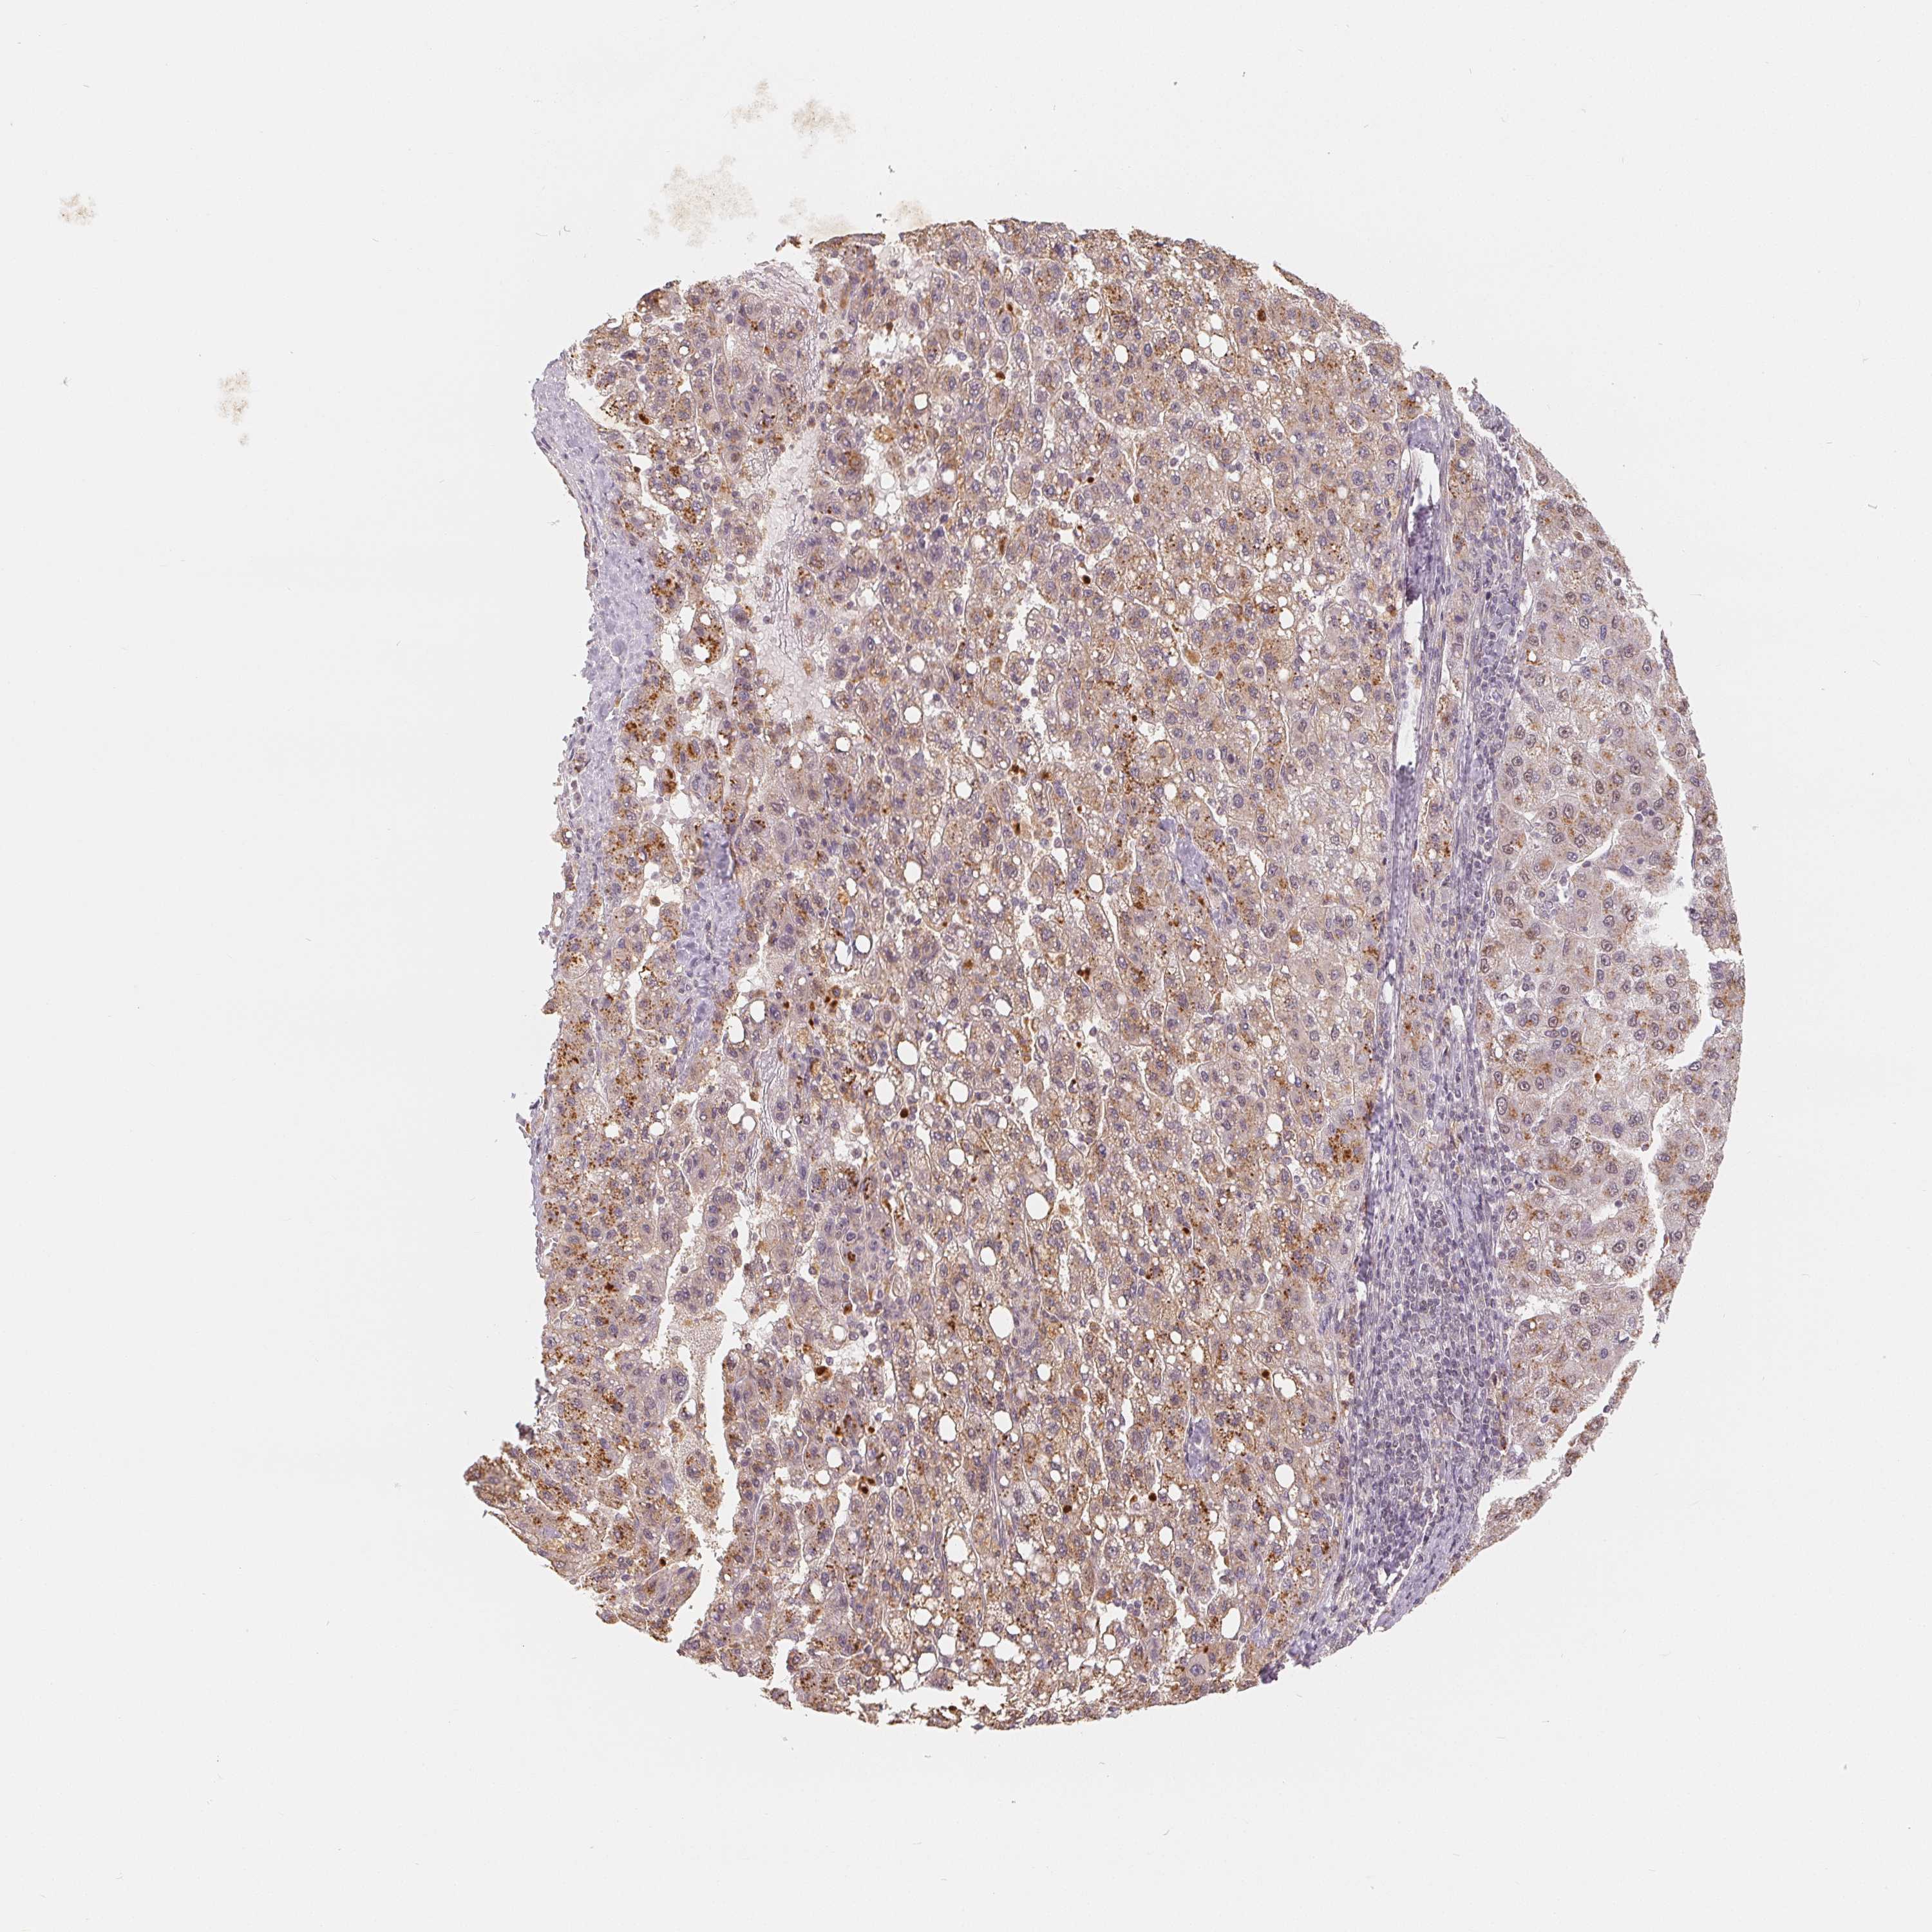

LIVER CANCER - Protein expressioni

A mouse-over function shows sample information and annotation data. Click on an image to view it in a full screen mode. Samples can be filtered based on level of antibody staining by selecting one or several of the following categories: high, medium, low and not detected. The assay and annotation is described here.

Note that samples used for immunohistochemistry by the Human Protein Atlas do not correspond to samples in the TCGA dataset.

Antibody stainingi

Antibody staining in the annotated cell types in the current human tissue is reported as not detected, low, medium, or high, based on conventional immunohistochemistry profiling in selected tissues. This score is based on the combination of the staining intensity and fraction of stained cells.

Each image is clickable and will lead to virtual microscopy that enables deeper exploration of all samples and also displays staining intensity scores, fraction scores and subcellular localization as well as patient and tissue information for each sample.

Antibody HPA036322

Antibody HPA036323

Staining

High

Medium

Low

Not detected

Intensity

Strong

Moderate

Weak

Negative

Quantity

>75%

75%-25%

<25%

None

Location

Nuclear

Cytoplasmic/membranous

Cytoplasmic/membranous,nuclear

Cholangiocarcinoma

Carcinoma, Hepatocellular, NOS